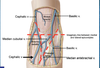

radial groove

On posterior side of midshaft of humerus

medial and lateral epicondyles

prominences of distal humerus on medial and lateral side of elbow

ulnar groove

groove in medial aspect of distal humerus for ulnar nerve

supracondylar ridges

extend superiorward from epicondyls; attachments for muscles of the forearm

intermuscular septum

separates arm into anterior (flexor) and posteror (extensor) compartments; medial and lateral; thick layer of fascia

triceps brachii

O: long head = infraglenoid tubercle, lateral head: posterior side of humerus superior to radial groove, medial head: posterior side of humerus inferior to radial groove, I: Olecranon of ulna, N: Radial nerve, A: extends the forearm (long head can also extent arm)